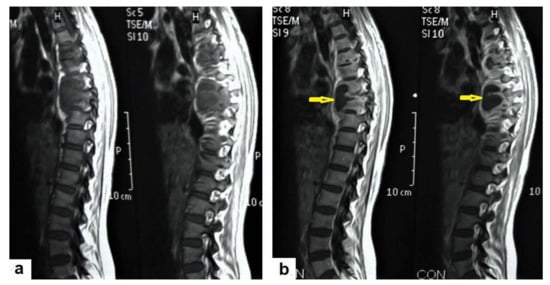

Figure 18. Pott’s disease in a 28-year-old female. Selected images of sagittal MRI of thoracic spine show destructive lesion affects multiple contiguous thoracic vertebrae with paraspinal collection. (a) Pre-contrast and (b) post-contrast T1-weighted images show subligamentous spread of the infection to involve five vertebrae with peripheral enhancement of the lesions, suggesting an abscess (arrow).

• Tuberculous spondylitis (Pott’s disease; Figure 18 and Figure 19) is a tuberculous infection of the spine that can affect any age and most commonly affects the lower thoracic and lumbar, followed by the cervical spine. It usually affects multiple contiguous vertebrae with paraspinal extension, causing subdural or epidural abscess formation and resultant spinal cord compression, which is a leading cause of paraplegia [27]. CT demonstrates the extent of bone involvement, while MRI demonstrates spinal-cord and soft-tissue involvement. Tuberculous spondylitis appears as a well-defined paraspinal abnormal signal intensity, as a thin wall abscess, or a combination of intraosseous and soft tissue abscesses. The spread of infection is sub-ligamentous beneath the anterior longitudinal ligament involving multiple vertebrae with high signal intensity on T2WIs. Pott’s disease is a difficult differential diagnosis with a spinal pyogenic infection. MRI demonstrate have 100% sensitivity, 80% specificity, and 90% accuracy in differentiating tuberculous from pyogenic spinal infection [34].